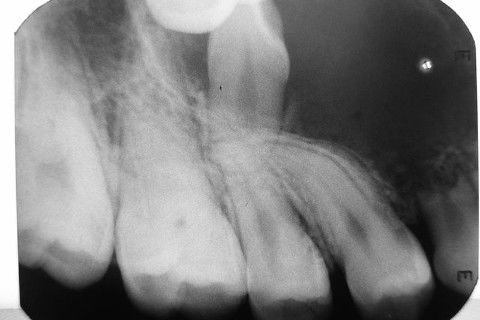

Rx periapical

Exames radiográficos sugerem imagem unicística, delimitada, circunscrita, 3 cm de extensão, associada aos dentes referidos acima.